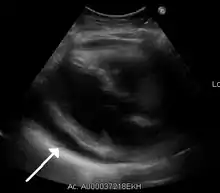

| A 2D echo transthoracic echocardiogram of pericardial effusion. The "swinging" heart. | |

Echocardiogram (ultrasound): when pericardial effusion is suspected, echocardiography usually confirms the diagnosis and allows assessment of the size, location and signs of hemodynamic instability.[4] A transthoracic echocardiogram (TTE) is usually sufficient to evaluate pericardial effusion and it may also help distinguish pericardial effusion from pleural effusion and MI. Most pericardial effusions appear as an anechoic area (black or without an echo) between the visceral and the parietal membrane.[1] Complex or malignant effusions are more heterogeneous in appearance, meaning they may have variations in echo on ultrasound.[5] TTE can also differentiate pericardial effusion based on the size. Although it's difficult to define size classifications because they vary with institutions, most commonly they are as follows: small <10, moderate 10–20, large >20.[5] An echocardiogram is urgently needed for evaluation when there is concern for hemodynamic compromise, a rapidly developing effusion or history of recent cardiac surgery/procedures.[1]

A large anechoic (black) pericardial effusion as seen on ultrasound. Closed arrow: the heart, open arrow: the effusion